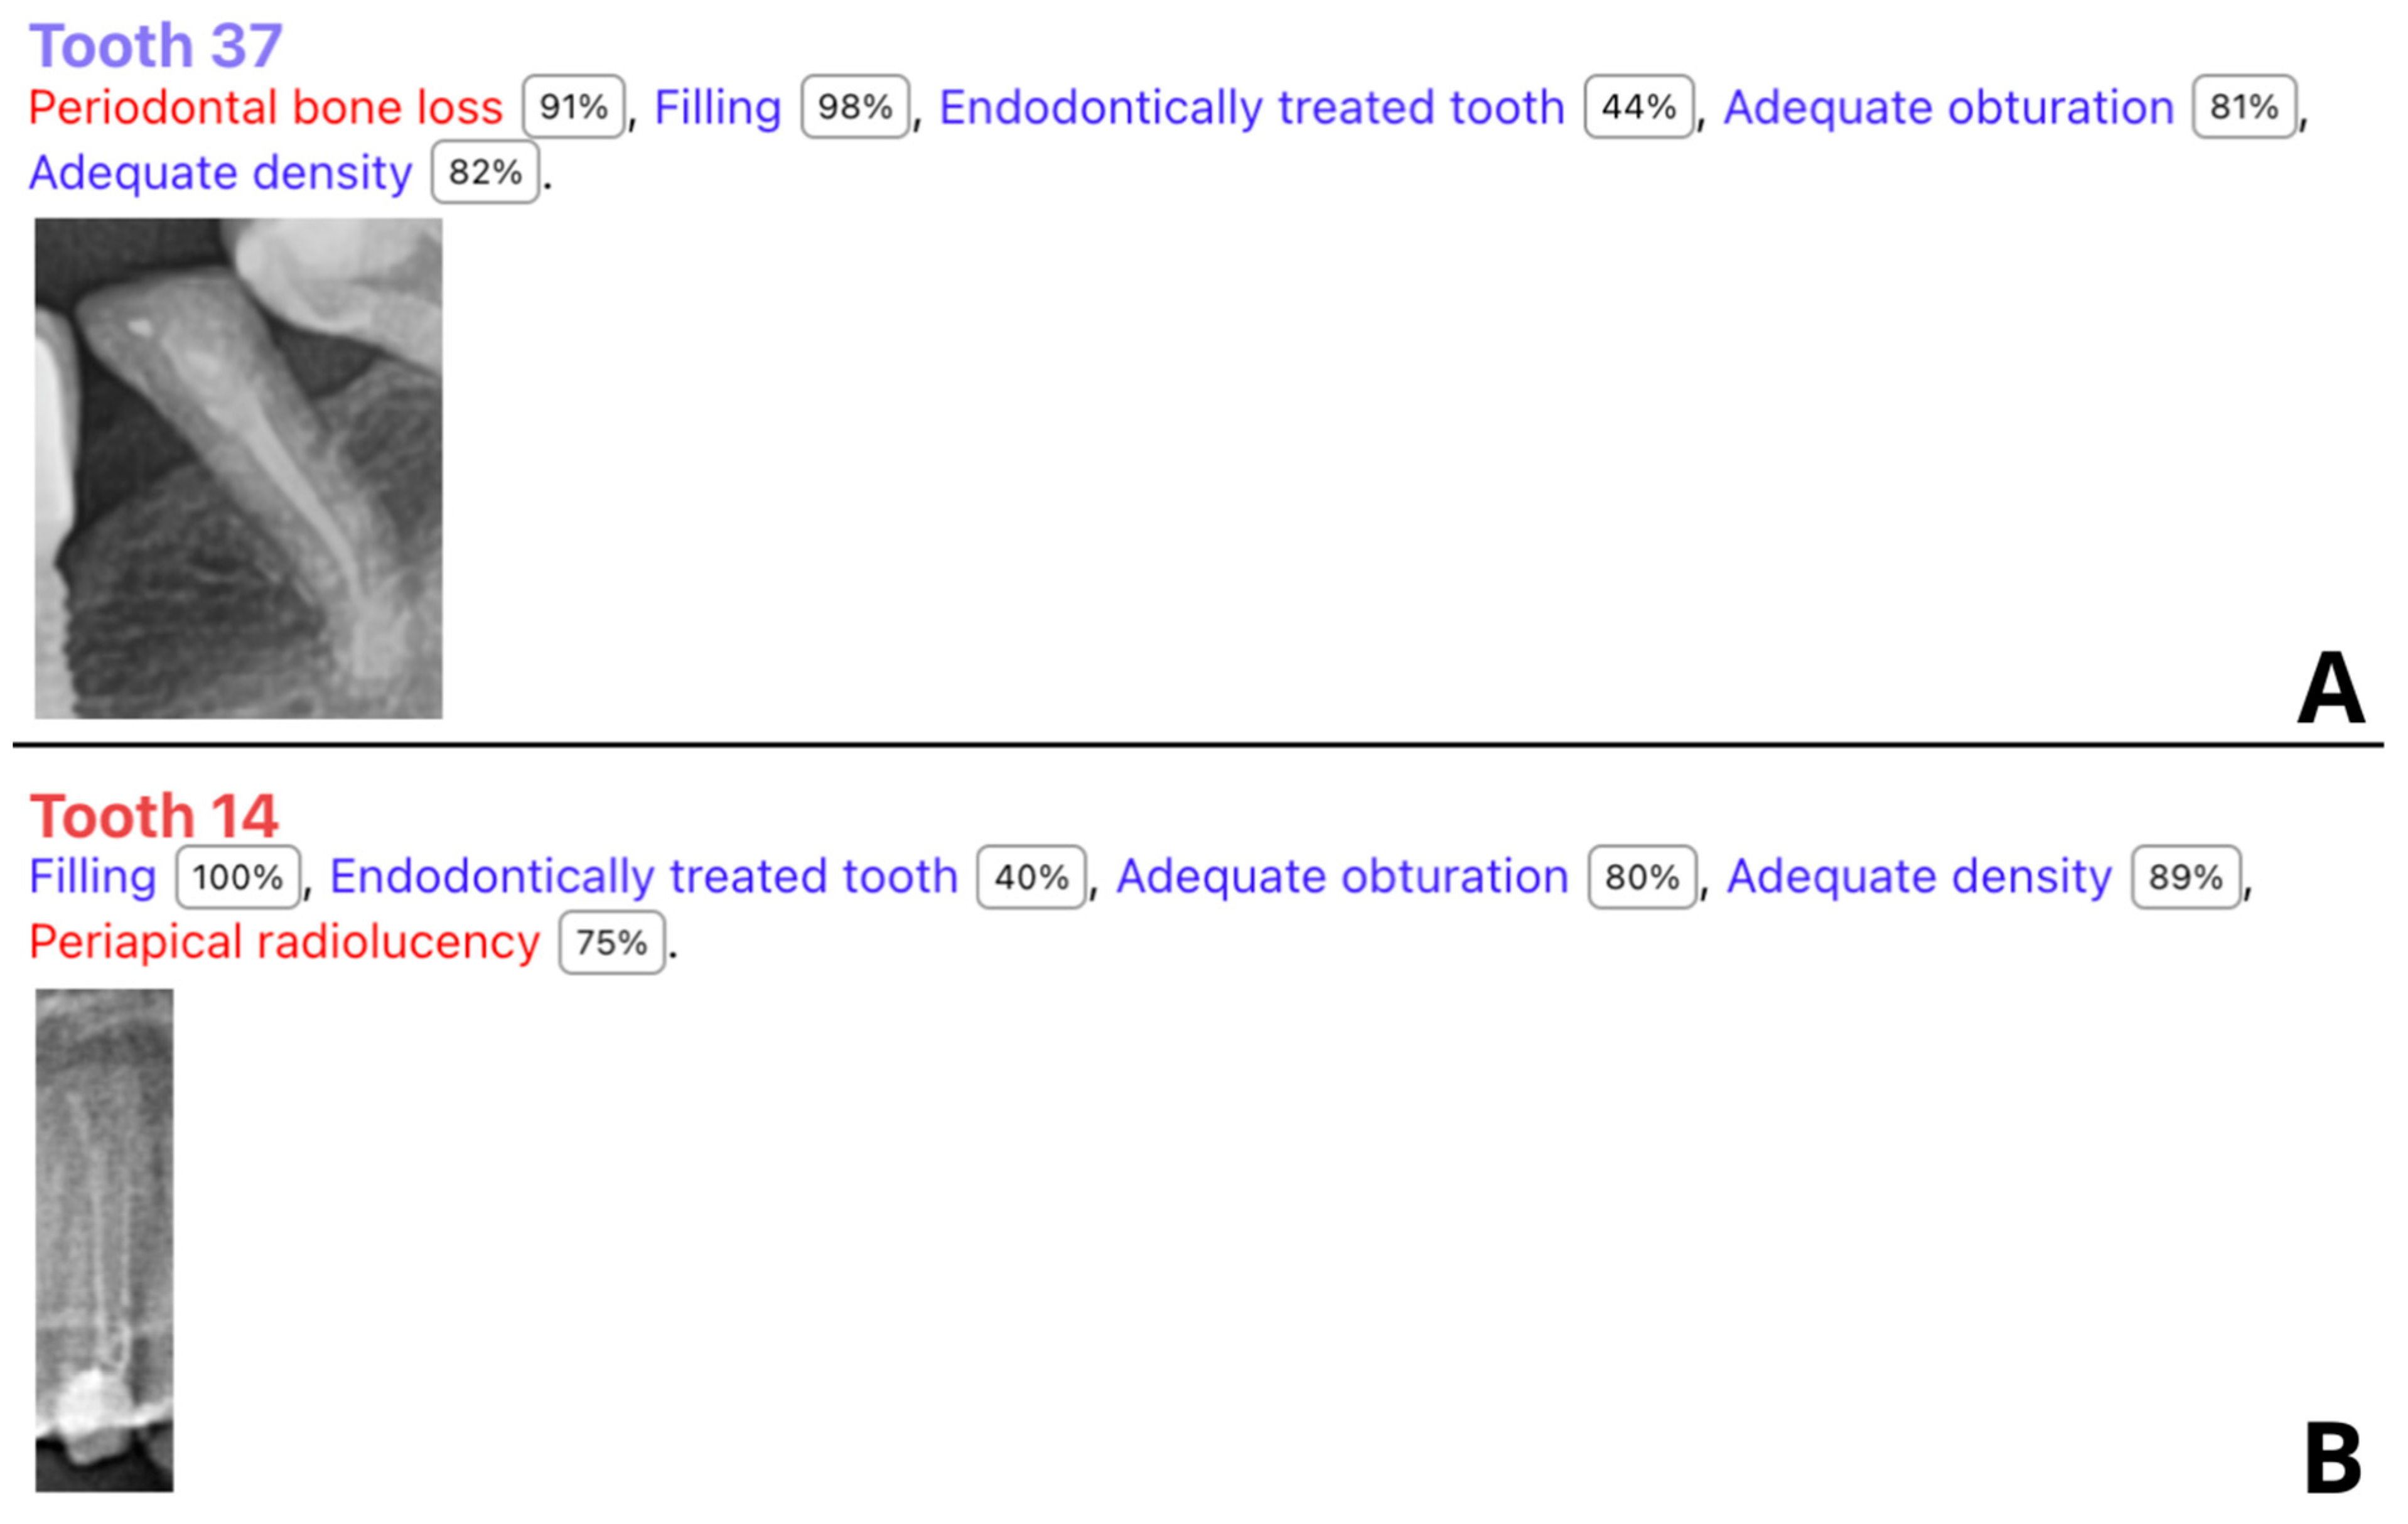

3. Results

3.2. Diagnostic Accuracy Parameters

4. Discussion